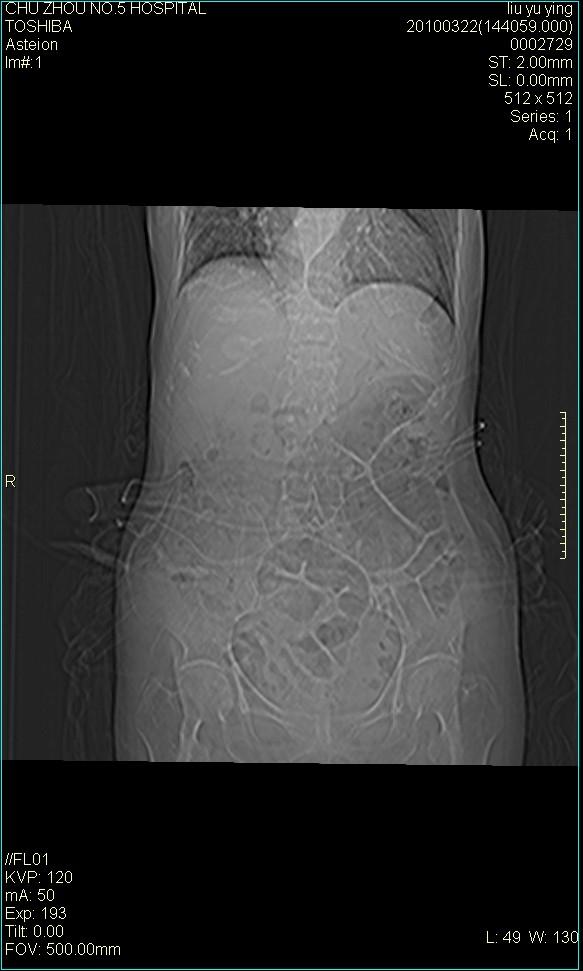

以下是引用科室第一人在2010-3-23 6:50:00的发言:[br]胆总管下段梗阻,多为肿瘤性病变,巨形胆囊,胆囊炎胆囊窝积液。[br]双侧胸腔积液,右降

以下是引用随光逐影在2010-3-23 8:12:00的发言:[br]1)胆系低位梗阻(肝内外胆管扩张,胆囊增大),原因待查。2)胆囊炎。3)双侧少量胸腔积液。4)降主动脉迂曲。